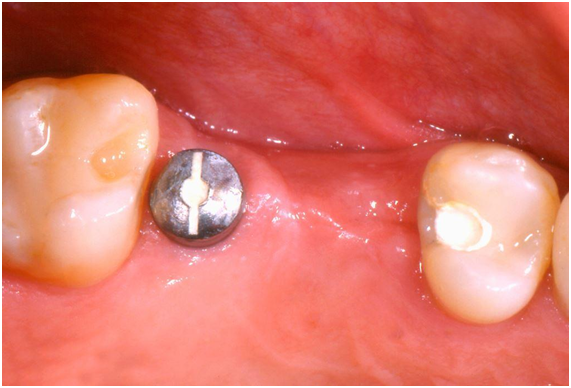

A 45-year-old female patient, after having undergone the installation of dental implants of the external hexagon type in the region of the right upper second premolar and first molar (Figure 1), presented the complaint of depression in the region of the implants, causing an aesthetic defect, visible when smiling (Figure 2). In the anamnesis, no relevant aspects were observed in the patient's previous and current medical history that could interfere in the diagnosis, treatment and prognosis of the intervention to be performed. The correction of the defect was performed after four months of the implants installation, using the technique of mucogingival surgery, in order to gain soft tissue in thickness. Prior to the surgical procedure, the patient received control of biofilm and orientation for maintenance of periodontal health. Then, a subepithelial connective tissue graft (SCTG) was performed using the roller technique. Local infiltrative anesthesia was performed by vestibular and palatine of the defect region using mepivacaine anesthetic 2% with vasoconstrictor. An incision was made with a 15C scalpel blade on the bony crest, further shifted to the palatine, and the dissection plane was crown-apical. Two other slightly divergent incisions were made in the palatal region to divide the epithelial flap. After splitting the flap, an incision at the base of the connective tissue attached to the periosteum was performed (Figure 3) to release the graft, which was moved to the receiving area (vestibular mucosa). The graft was folded under the vestibular flap (Figure 4) and stabilized with isolated suture at the base of the flap. Healing abutments were installed. The vestibular flap was repositioned around the abutments with the graft stabilized by the suture, also performed on the sides and at the base of the wound with interrupted stitches of resorbable Vicryl 5.0 (Figure 5). Compressive suture was performed on the palate over hemostatic sponge of hydrolyzed collagen (Figure 6). The postoperative period consisted of orientations to the patient regarding hygienic care, feeding, rest and prescription of analgesic (paracetamol 750 mg) and anti-inflammatory (nimesulide 100mg). Chemical control of bacterial plaque was also prescribed by means of two 1-minute daily mouthwashes at twelve-hour intervals with 0.12% chlorhexidine digluconate. Patient returned to the postoperative period after seven days, and the suture was removed after 14 days. Patient was kept under control for 30 days, and she was referred for prosthetic rehabilitation after 4 months of surgery. With two months of proservation, tissue gain was observed in thickness (Figure 7). For gingival tissue conditioning, a provisional prosthesis was installed after three months of the mucogingival surgery (Figure 8). It was observed that, after the 6-month period of proservation, the tissue gain in thickness by the SCTG favored the vestibular emergency profile of the prosthesis and the new conformation of the gingival papillae (Figure 9) (Figure 10) (Figure 11).

Figure 1 Clinical aspect of the region showing the first molar implant healing abutment and the second premolar submucosal implant.